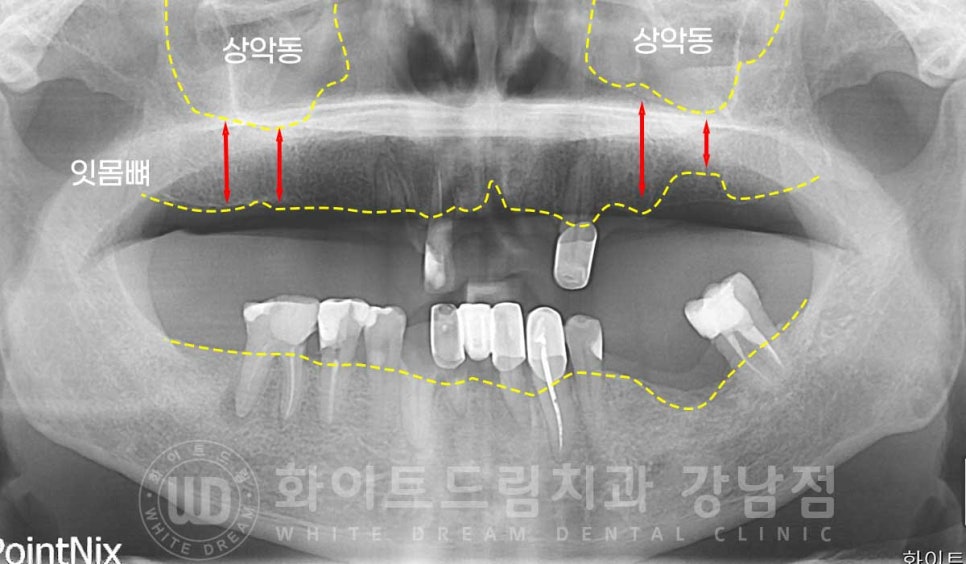

상악동의 경우 개인마다 모양, 위치, 크기가 각기 다른데

환자분의 경우 상악동의 위치가 높게 자리를 잡고 있는 상태입니다.

상악동이 높게 자리를 잡고 있으면

잇몸뼈의 길이가 임플란트를 식립하기에 적합하여 뼈이식 없이 수술이 가능한 경우들이 있습니다.

환자분의 경우 골 길이는 안정적이나

잇몸 염증으로 상악의 골폭 소실이 진행된 상태였습니다.

▲ 상악, 골폭이 모자란 부위

잇몸뼈의 길이가 임플란트를 식립할 수 있을 정도로 남아있지만

골폭이 모자란 경우는 임플란트를 감쌀 만큼의 충분한 잇몸뼈의 두께가 모자라다는 것으로

식립 후 나사선이 겉으로 잇몸뼈 밖으로 노출되기에

뼈이식, gbr(guided bone regeneration)을 동반하게 됩니다.